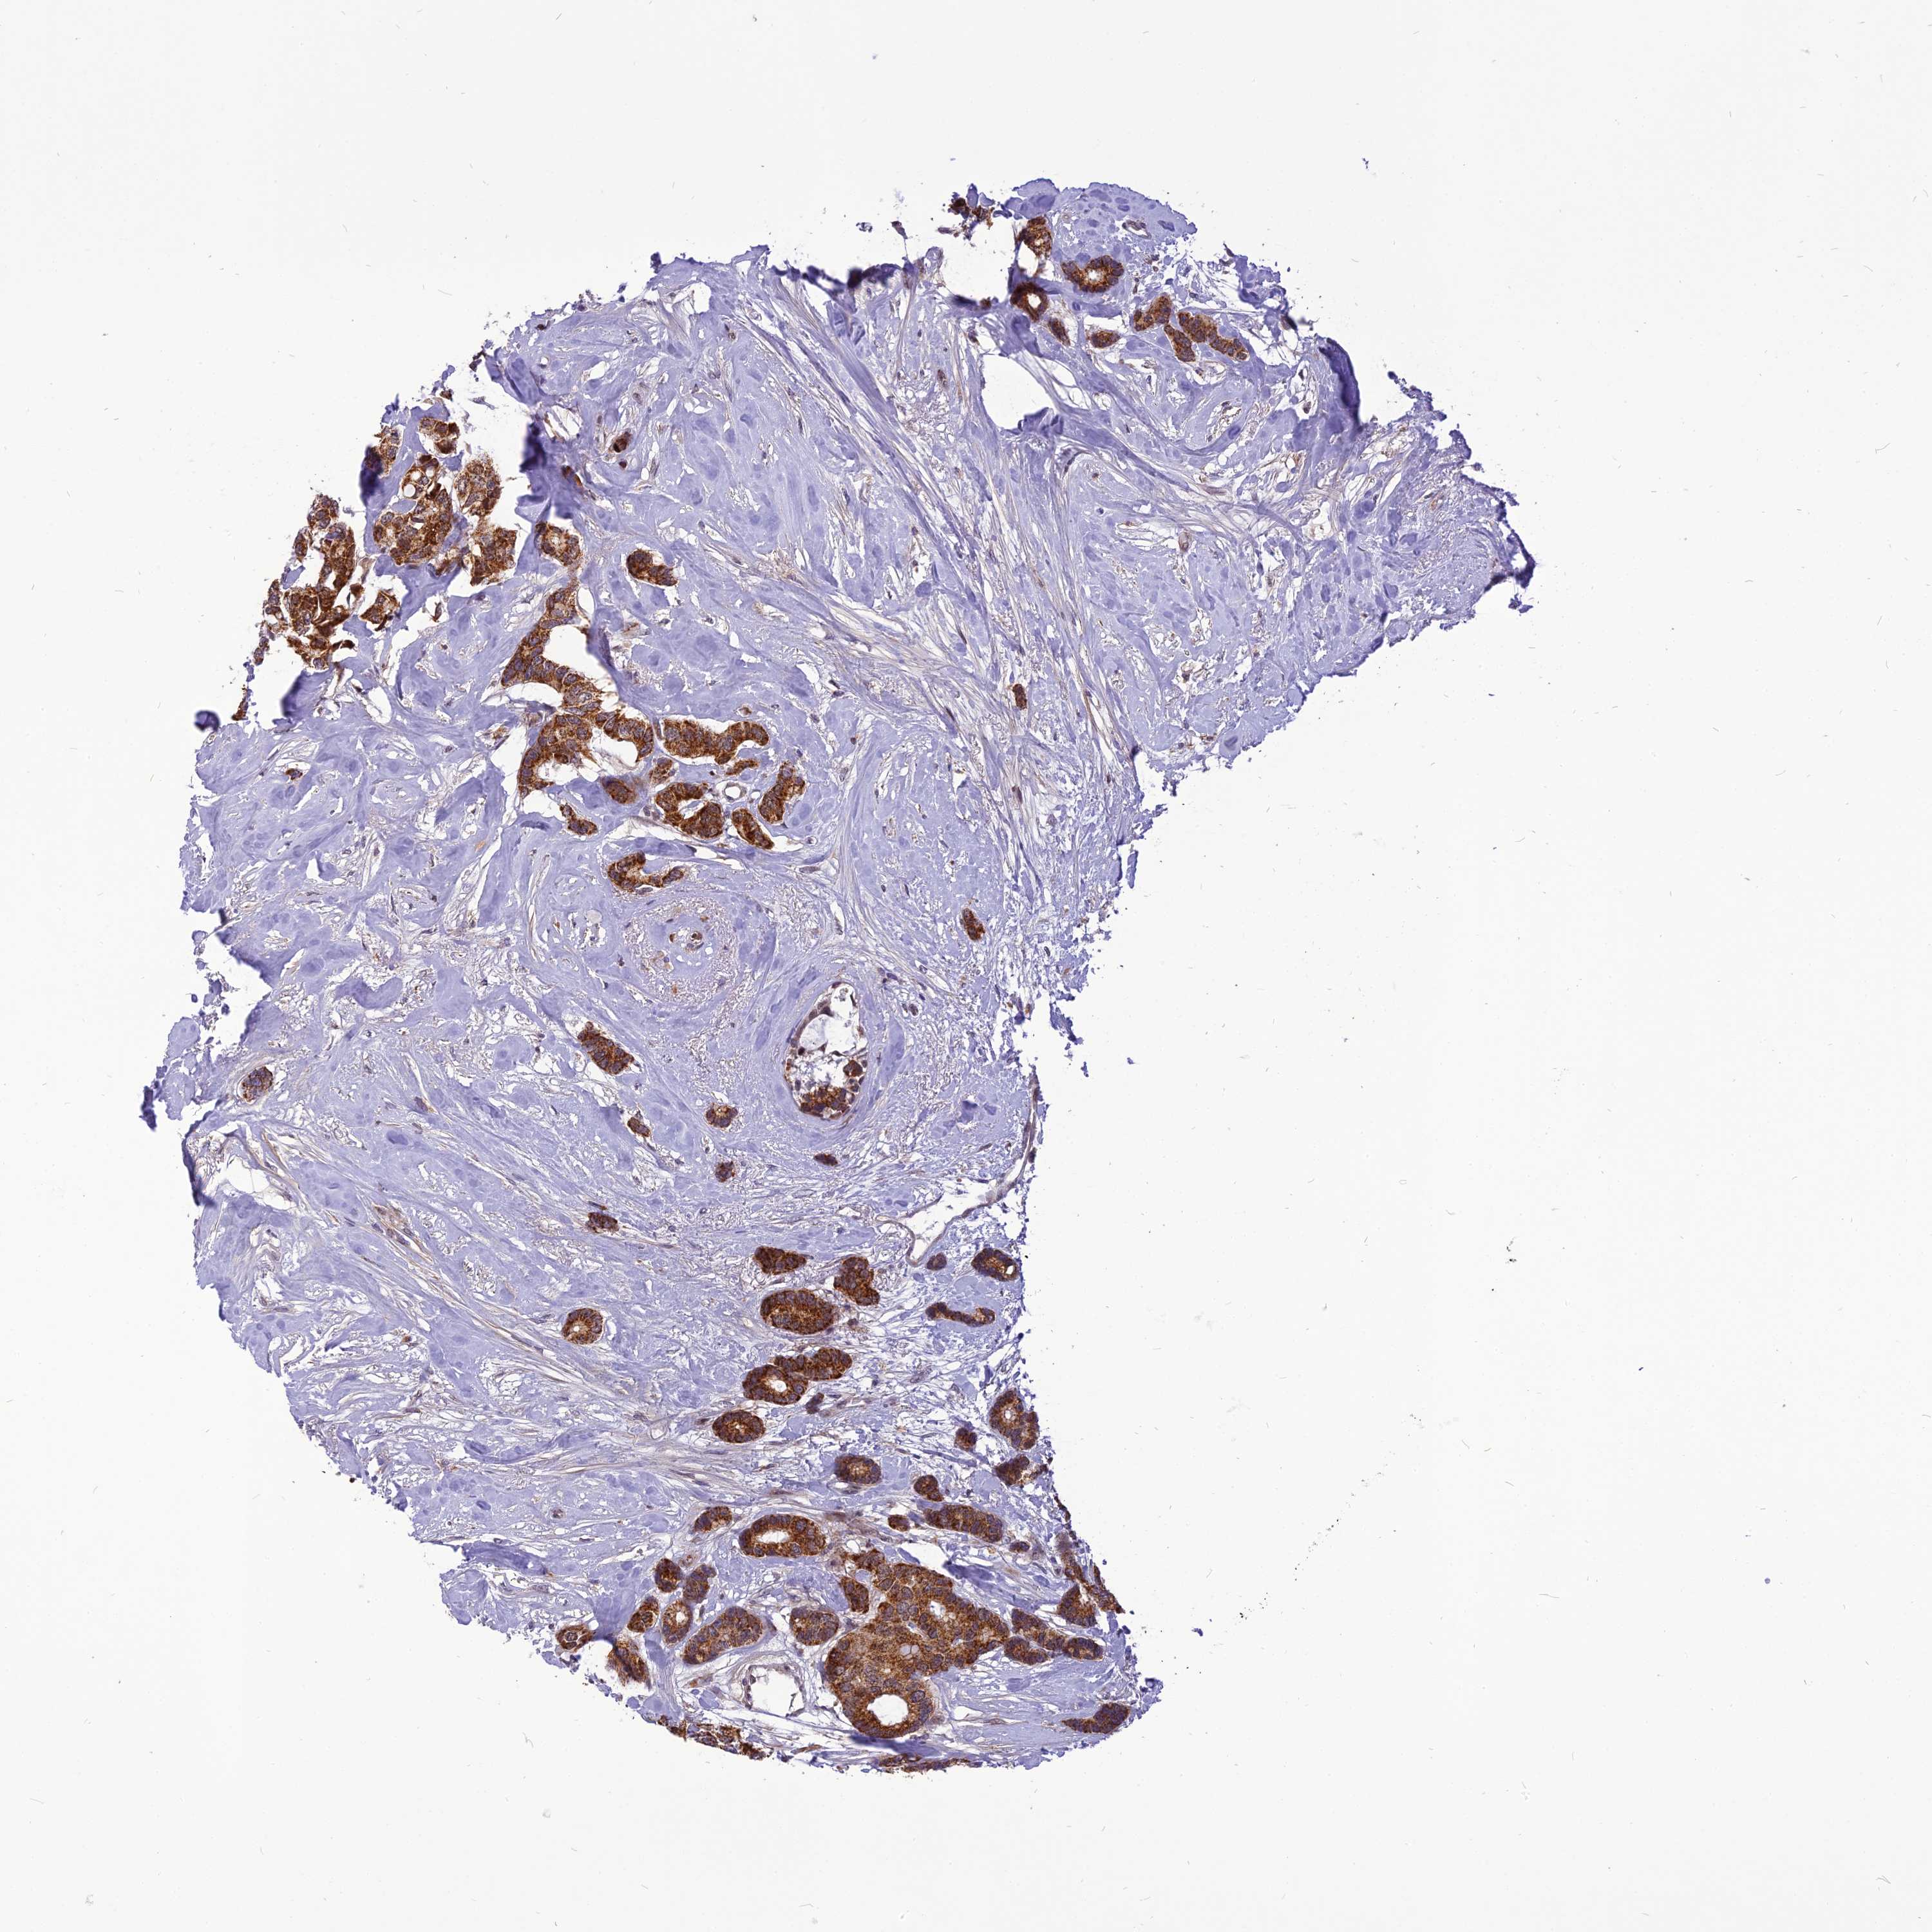

CANCER BREAST CANCER Show tissue menu

BRCA TCGA BRCA VALIDATION PROTEIN EXPRESSION

Breast cancer

Human cancer

CMC1 is potential prognostic, high expression is unfavorable in Breast Invasive Carcinoma (TCGA)